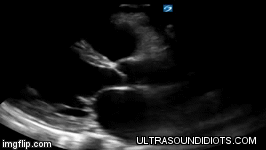

Examples of reduced and Hyperdynamic LVEF